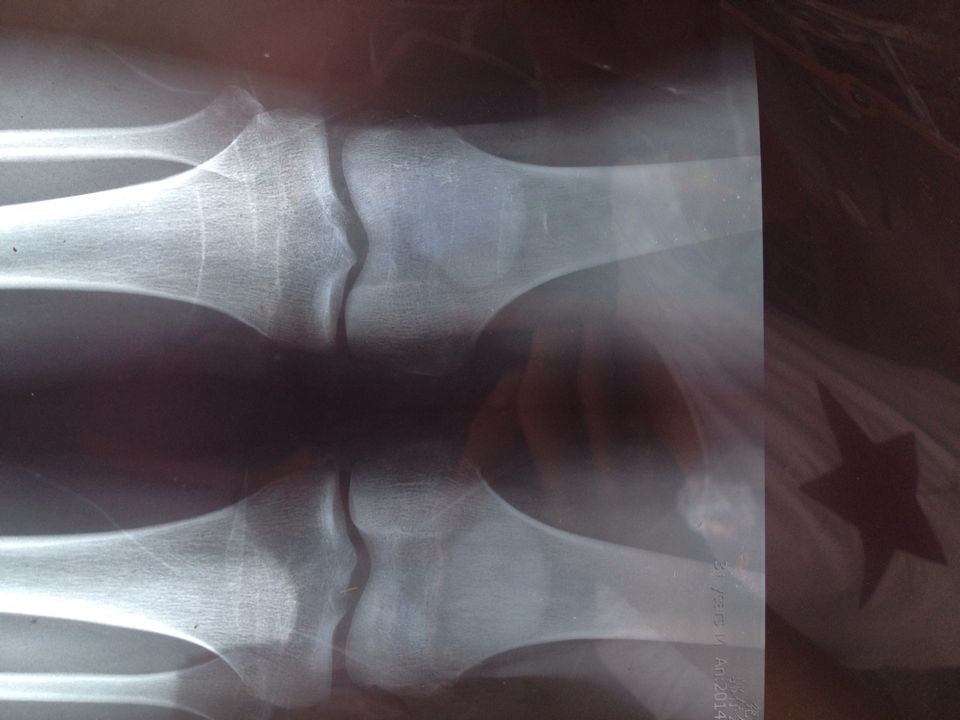

2、X光檢查:X光檢查是判斷骨骺線是否閉合的最準(zhǔn)確方法,通過拍攝手腕或膝關(guān)節(jié)的X光片,可以清晰地觀察到骨骺線的狀況,如果X光片中顯示骨骺線已經(jīng)消失,說明骨骺線已經(jīng)閉合。